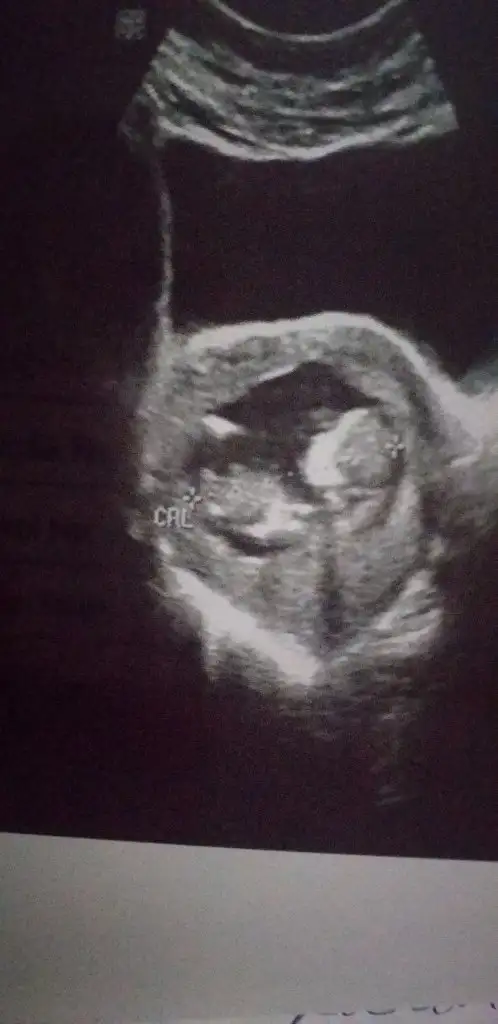

kese konumuna göre de zaten erkek demiştin bir usg de nubu kız gibi ama emin değilim paralel de değil dikte dedin görüntüsü erkek dedin en son USG de pipi var dedin evet doğru görmüşsün bu gün doktorda gösterdi :) Kızımda zaten doğru bilmiştin oylamıştım O zaman bizde tahminlerin doğru çıktı teşekkür ederiz teyzesi :)

Net değil varsa 11 12 hafta paylaşın sanki sanki kız diyecem emin olamadımEki Görüntüle 2693607 Bana da tahminde bulunurmusunuz 13 haftalık burda

Başka resim yok maalesefNet değil varsa 11 12 hafta paylaşın sanki sanki kız diyecem emin olamadım